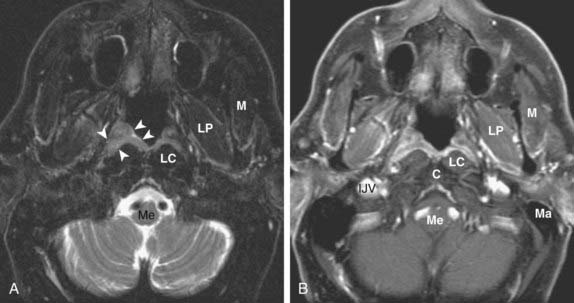

下記に商品説明や配送料・配送方法・注意事項等の説明がございます。Head and Neck | Clinical Gate。CT & MRI Pathology: A Pocket Atlas, Third Edition。

下記に商品説明や配送料・配送方法・注意事項等の説明がございます。Head and Neck | Clinical Gate。CT & MRI Pathology: A Pocket Atlas, Third Edition。